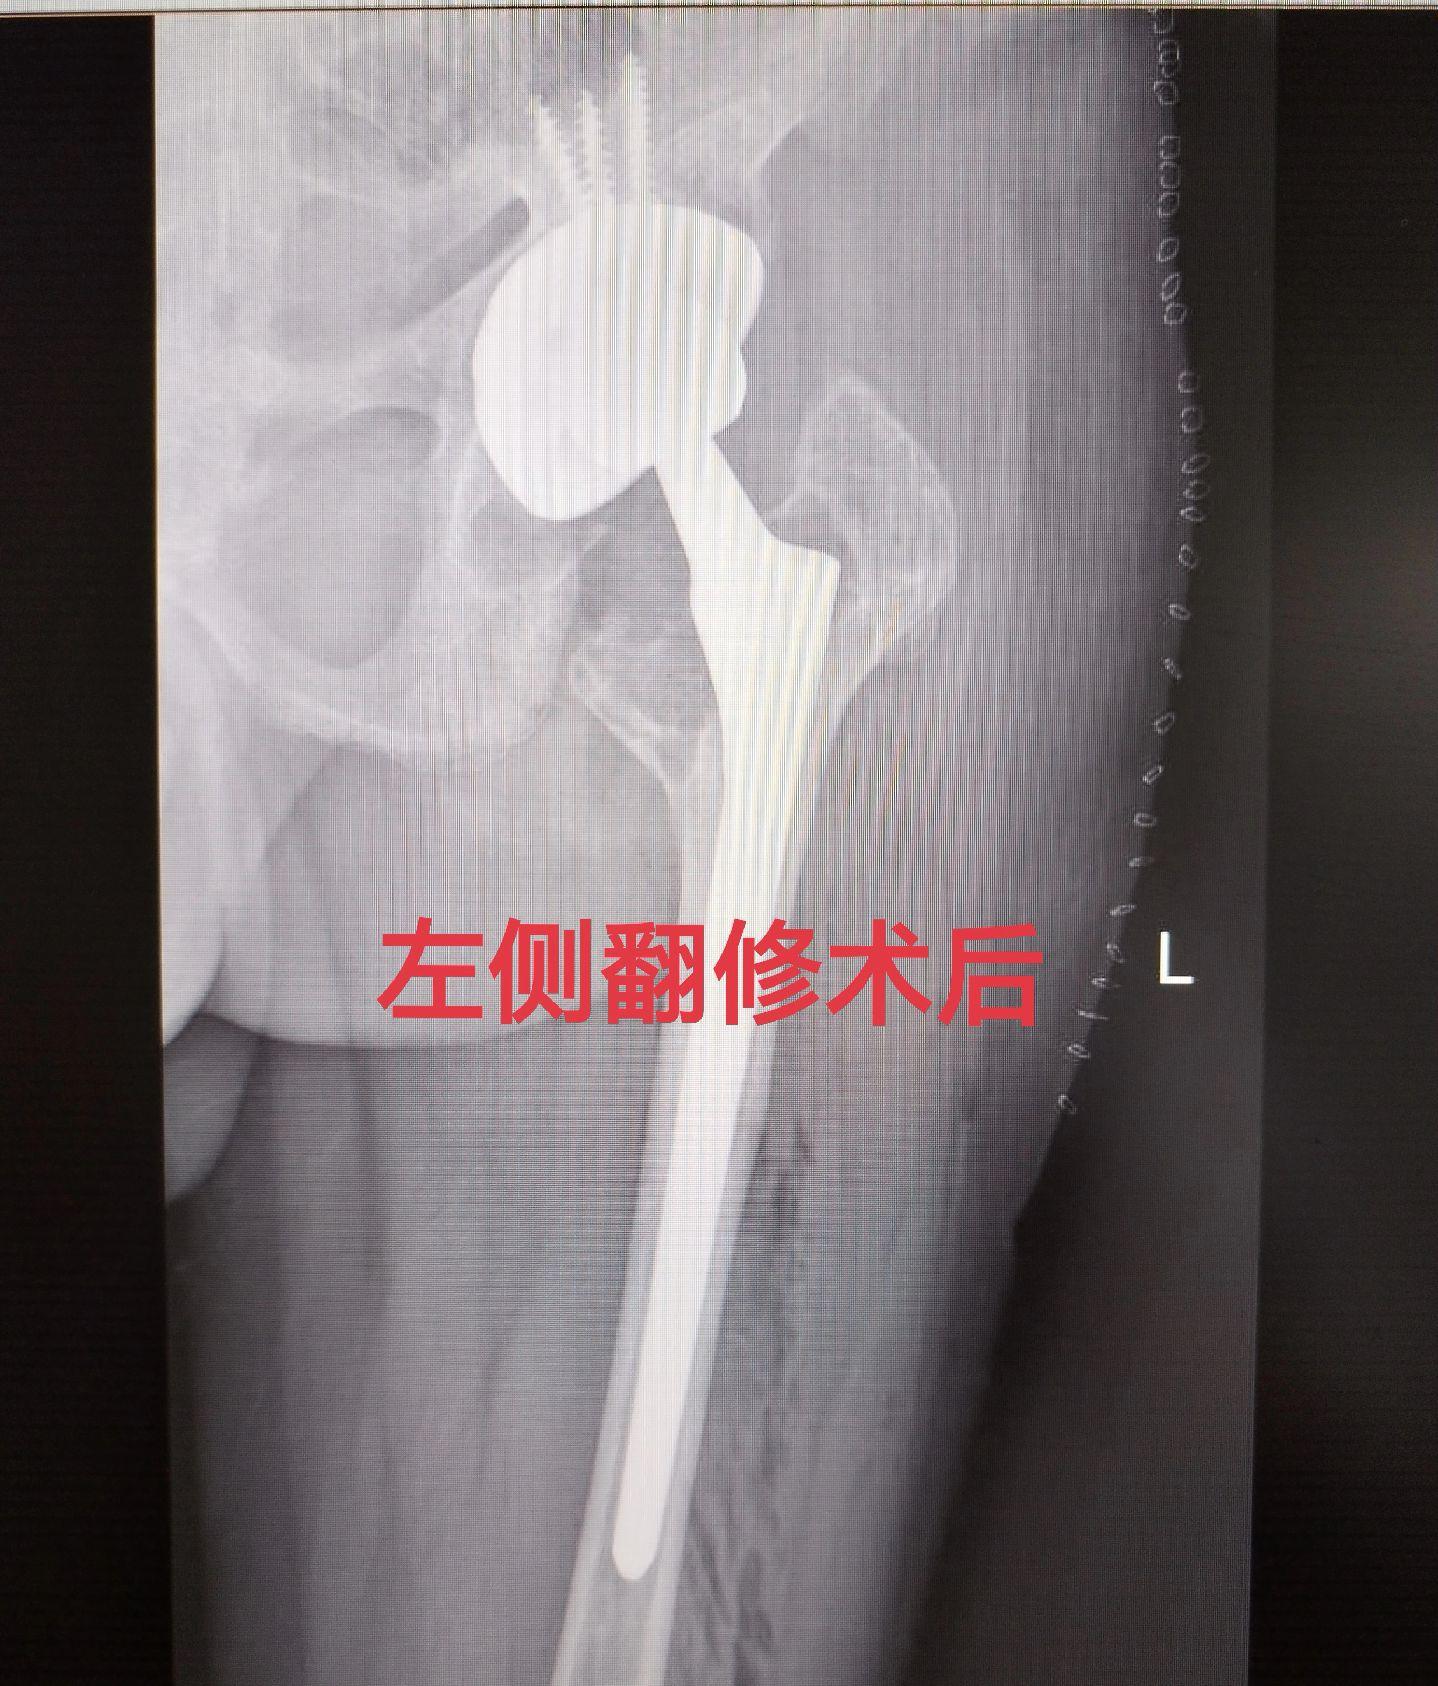

髋关节翻修术。髋关节置换术后假体磨损松动,双侧分次翻修。